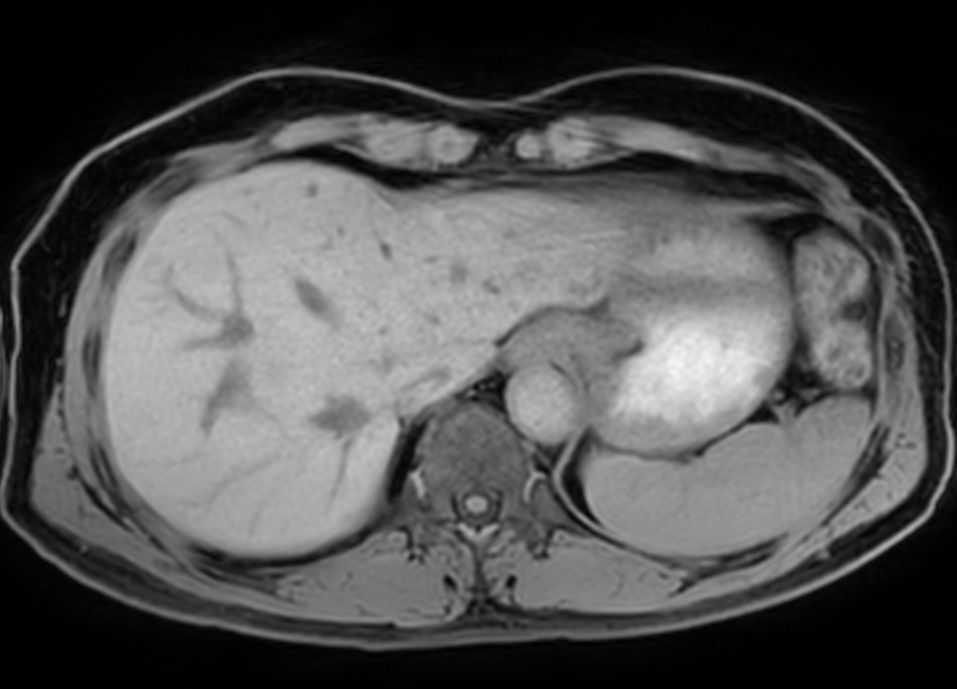

Axial Dual FFE (In Phase)

-

Axial Dual FFE (Out Phase)